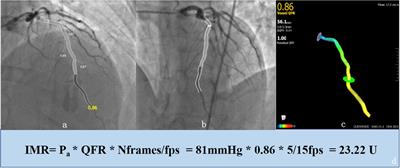

Published on 12 Apr 2022

in Computational Physiology and Medicine